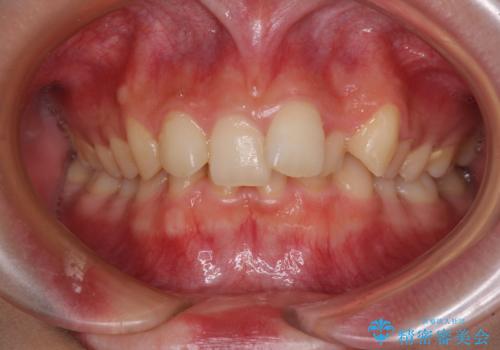

- 下顎前歯が欠損しており、前歯がデコボコとなっている歯並びを気にして来院された患者様です。

下顎の左右側切歯2本が欠損しており、上顎歯列がデコボコとなっている状態でした。

下顎歯列に対して上顎歯列が相対的に大きくなっているため、デコボコとなっているだけでなく、下顎前歯が見えなくなるくらいのディープバイトにもなっていました。